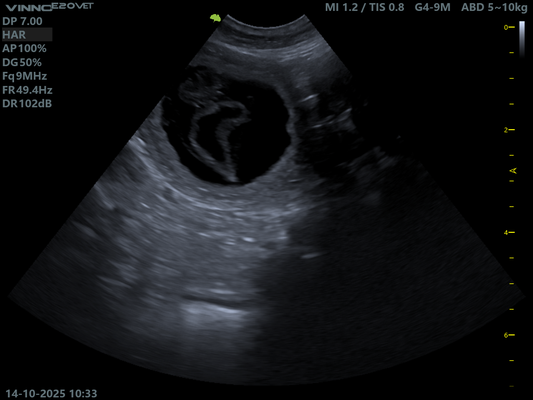

14.10.2025 Ultraschall Untersuchung.

Schon nach einem kurzen Blick in Ruby's Bauch war klar.

Sie ist tragend!

Doch wie viele es werden bleibt bis zuletzt spannend.

Hier müssen wir uns absolut keine Sorgen machen. Ruby scheint einen normalen Wurf zu erwarten, so auch die Aussage unserer Tierärztin.